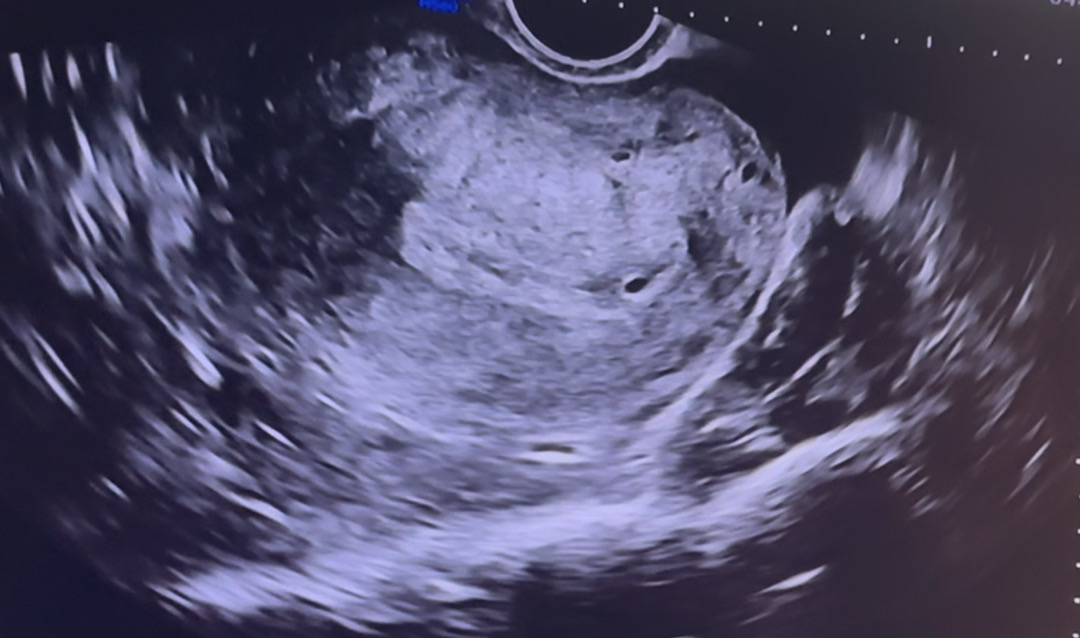

5주차1일 자연임신 아기집 안보임

마지막 생리일 8/21 이번주월요일 22일에 두줄확인하고 바로 병원갔더니 자궁벽은 두꺼워져있는데 아기집 안보인다고 일주일뒤에오라했었어요 그 병원 맘에안들기도했고 병원 옮길겸 오늘 9/26 다른병원갔는데 아직 아기집 안보인다고 ㅠ 피검사하고가라해서 했는데 피검사결과는 내일 전화로 알려준대요… 아직 안보일수 있는거겠죠? 4일동안 우리애 초등학교까지 보냈는데 엉엉 ㅠ 다음주가면 보일까요… 근데 사진상 저거는 아기집이 아닌가봐요? 초음파찍는거 영상촬영했는데 괜히 희망품어요ㅠ

저게 아기집 아니면 모가 아기집이래여 👀

저거 아기집 맞는것같은데여 저도 저랬어용 너무 작아서 확답을 안주셨다봐요